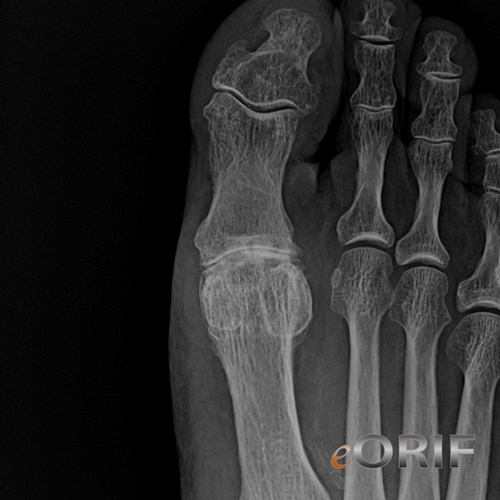

Center for Ankle and Foot Care Blogspot Are you frustrated with impending ICD10 quickly. It is found in the 2022 version of. M20.11 is a billable icd code used to specify a diagnosis of hallux valgus (acquired), right foot.

Subscribe to codify by aapc and get the code details in. Available for iphone, ipad, android, and web. 8 735.0 hallux valgus (acquired) m20.10 hallux valgus (acquired) unspecified foot m20.11 hallux valgus (acquired) right foot m20.12 hallux valgus (acquired) left foot

The icd10 code for the diagnosis hallux valgus (acquired), right foot is m20.11. It is found in the 2022 version of the. 2016 2017 2018 2019 2020 2021 2022 billable/specific code.